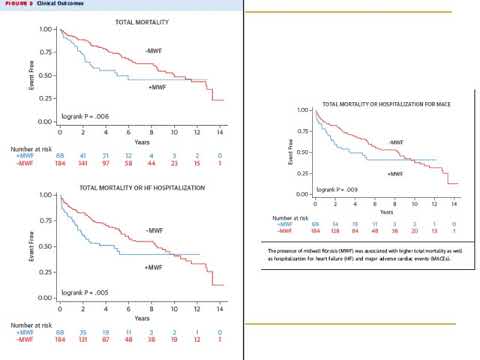

Implicaciones pronosticas de la FA en insuficiencia cardíaca con función sistólica reducida. Dra. María Victoria Vannoni. Residencia de Cardiología. Hospital C. Argerich. Buenos Aires